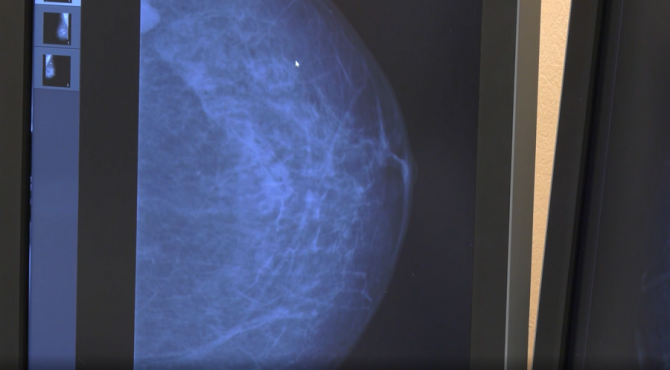

Важно, что молочные железы проверяют в нескольких проекциях. Техника позволяет сделать прицельные снимки или томосинтез, такая диагностика позволяет выявить не только онкологию, но и сигнализировать о других заболеваниях.

«Мы обязательно указываем, если видим кальциноз стенок сосудов в молочных железах. Это сигнал для кардиолога, что нужно обследоваться. У молодых такое тоже встречается», – рассказывает врач-рентгенолог Ирина Главатских.